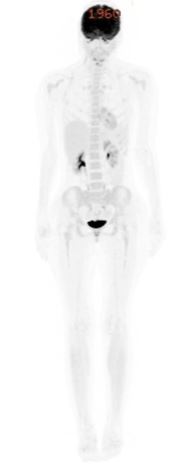

D+45 post-transplant assessment showed complete molecular remission on PET scan and Minimal Residual Disease (MRD) negativity by bone marrow biopsy (Figure 4).

Figure 4: PET CT post allogenic stem cell transplantation suggestive of a complete metabolic response.